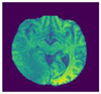

A brain tumor can be defined as a cancerous or noncancerous mass or development of abnormal cells in the brain. Gliomas can be categorized into High-Grade Glioma (HGG) and Low-Grade Glioma (LGG), based on the pathological assessment of the tumor. Brain tumor segmentation seeks to separate healthy tissue from tumorous regions. This is a crucial step in analysis and treatment planning to improve the possibility of effective treatment. Nowadays, biological science has emerged with several extended research problems under the category of Digital Image Processing (DIP). The detection of the tumor and its classification, detection of the cancerous region and its classification, testing, and inspecting crucial parts of the human body are some applications that fall under this category. Out of various medical science problems, automatic brain tumor segmentation and detection is of utmost importance, and efforts are being made in order to effectively handle this problem. A January 2020 Cancer.net editorial approved a report that estimated that this year, 23,890 adults, i.e., 13,590 males and 10,300 females, will be identified with cancerous tumors of the brain and spinal cord in the USA. In general, brain tumor diagnosis usually starts with Magnetic Resonance Imaging (MRI). The suspicious regions are separated using magnetic resonance segmentation using a complicated clinical imaging process. MRI is the most commonly used process that highlights the tumorous region in the brain, although brain tumor detection is still a manual process, examined and validated by experts. Thus, we require a compelling process to identify brain tumors in the early stage to save patients with high accuracy. There are some issues in the manual process, due to which the automatic detection of brain tumors becomes pivotal. Computer-aided detection of abnormal growth of tissue is primarily motivated by the necessity of reducing human error and thus achieving maximum possible accuracy. Using automated algorithms for the accurate and robust predictions of overall survival for patients diagnosed with gliomas can provide valuable guidance for diagnosis and necessary treatment. Furthermore, there is a lack of skilled Oncologists and Neurologists, especially in developing countries. According to a report in 2018, the country is facing a severe shortage of caregivers, with merely 2000 oncologists looking after around 10 million patients (https://timesofindia.indiatimes.com/india/India-has-just-2000-oncologists-for-10-million-patients/articleshow/50842842.cms). Owing to the presence of abnormalities, no conventional technique can be developed for the segmentation of brain tumors in the medical field. Generally, magnetic resonance image (MRI) scans are utilized for the proper examination and diagnosis of brain tumors. This study systematically works on the detection of brain tumors using MRI images []. Owing to the profound significance of machine learning and deep learning, a vast number of methods have been developed, mostly using a specific technique, i.e., machine learning or deep learning []. Despite initiating a breakthrough in handling tumor detection tasks, existing applied deep learning models have some drawbacks. CNN-based deep learning techniques require high volume data, which makes it a complex and expensive task. Massive features are necessary to train tumor detection and segmentation accurately. However, the U-net model of CNN has shown great help in prognosticating in medical image segmentation. In recent literature, numerous works are done either using variation in U-Net architecture or with some pre/post-filtering for outcome improvisation. A Multi-Inception-UNet architecture is proposed to improve scalability and is applied to BraTs 2015, 2017, and 2019 datasets []. This is considered the latest work done in this same direction with the help of this same U-Net Model. MRI Brain Tumor segmentation is validated using 3D-UNet on the BraTs’20 dataset, where the author achieved an accuracy of 0.83 on the training set and 0.82 on the validation set []. The proposed work is somewhat motivated by the work done by Jurdi et al. in June 2020; in their work, U-Net with Bounding Box Prior is applied to two public datasets—SegTHOR is Computed Tomography (CT) images and another Cardiac dataset is a mono-modal MRI dataset. A bounding box (BB) filter is inserted at the BBConV Layer, by which researchers can achieve approximately 98.32% average dice coefficient []. Henceforth, in this study, a systematic process is performed for the detection of brain tumors using MRI images. The experimentation uses U-Net to exhibit the knowledge of deep learning models for tumor image segmentation. The deep learning model is applied for MRI segmentation on the BraTS 2018 dataset (https://www.med.upenn.edu/sbia/brats2018/data.html), which contains four different MRI modalities—T1, T2, T1Gd, and FLAIR of each patient (see Figure 1).

Figure 1.

A sample set of T1, T1-GD, T2, and T2 Flair images (Source: BraTS 2018 Dataset).

Corresponding to each patient, the segmented tumor region and OT (ground truth of tumor segmentation) are stated. Although experiments are primarily carried out on the BraTS dataset, a list of datasets used to perform brain tumor detection tasks is also tabulated in Table 1 for the readers’ point of view.